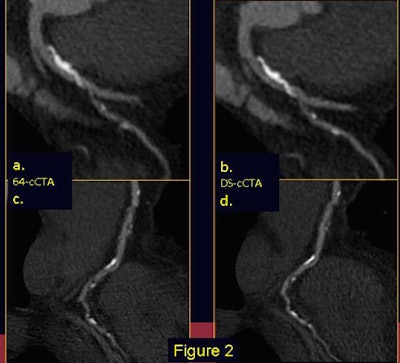

| Coronary CTA images were acquired with 64-slice single-source (left) and dual-source CT (right) technique. In a 62-year-old man, the presence of calcifications makes the degree of stenosis difficult to evaluate. Better discrimination of both calcifications and coronary lumen obtained with DSCT clearly defines irregularities. Invasive angiography study (bottom image) confirms moderate stenosis at this level. All images courtesy of Dr. Nicola Galea. |